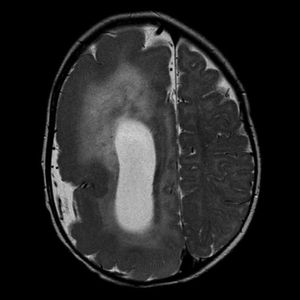

One-half of the brain abnormally bigger than the other half - that's a super rare cortical developmental disorder called hemimegalencephalgy! Notice this MRI of the brain which demonstrates the right cerebral hemisphere to be markedly enlarged. The grey matter is disorganized and thickened, consistent with migration arrest. The right lateral ventricle demonstrates an abnormal morphology and is also markedly enlarged. There is diffuse T2 hyperintensity throughout the white matter of the right hemisphere. The right cranial vault is also expanded.Additionally the right cerebellar hemisphere is also enlarged with abnormal cortical formation and the midline is shifted to the left. The left hemisphere is essentially normal in appearance.As a consequence of this size and structural differences, the enlarged brain tissue causes frequent seizures, often associated with cognitive or behavioral disabilities. The affected side can be surgically removed (anatomic hemispherectomy) or disconnected from the other brain structures (functional hemispherectomy). In such case, the remaining side of the brain may gradually take over the functions normally performed by the affected side.